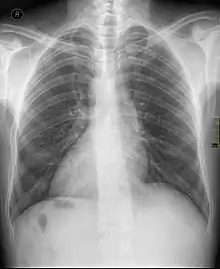

Dextrocardia

La dextrocardia es una situación en la que el corazón se encuentra en la mitad derecha del tórax debido a una causa de una alteración congénita.[1] Normalmente, el corazón se sitúa en la parte media del tórax, con su vértice o ápex inclinado hacia la izquierda; sin embargo, en esta malformación, ese orden es alterado y el corazón se ubica inclinado hacia el lado derecho del tórax. A menudo se asocia con otras anomalías del desarrollo y, en la mayoría de los casos, se diagnostica de forma incidental. Puede ocurrir por sí solo o puede ir acompañado de una inversión en la posición de otros órganos (denominado situs inversus totalis).[2]